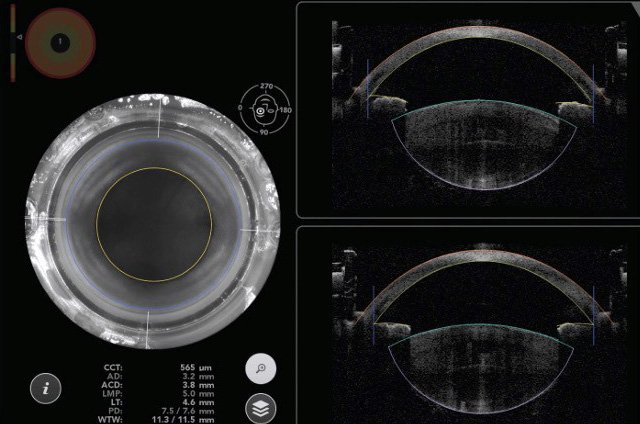

隨年齡增長,白內障發生率上升。傳統手術透過超音波乳化技術去除混濁的水晶體(白內障),並植入人工晶狀體。然而,近年高階白內障手術技術提供更精確、微創及更多功能的選擇。

眼睛是極其精密的器官,白內障手術需要精確到微米級。

眼球微小,角膜大約長寬一公分,手術涉及微米級的精細操作,因此我們經常提醒患者,在手術過程中需要保持安靜。只需閉眼休息,放空思緒,剩下的交給我們來處理。